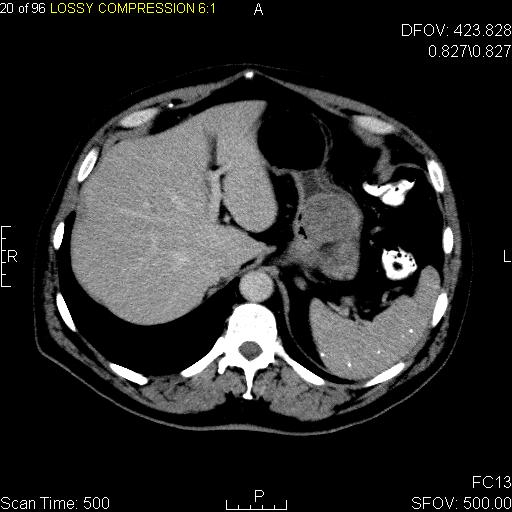

CT 스캔과 MRI는 GIST를 평가하는 데 선호되는 영상 검사 방법이다. 작은 GIST는 대개 점막하 종양 또는 장벽 내 종괴로 나타난다. 바륨 연하 검사에서 이러한 GIST는 인접한 장벽과 직각 또는 둔각을 이루는 매끄러운 경계로 나타나며, 점막 표면은 대개 손상되지 않지만, 50%에서 궤양이 나타나기도 한다. 궤양은 바륨으로 채워져 과녁 또는 표적 병변처럼 보인다. 조영 증강 CT에서 작은 GIST는 균질한 감쇠를 보이는 매끄럽고 선명하게 정의된 장벽 내 종괴로 보인다.큰 GIST는 장 밖으로 튀어나오거나 장 내부로 성장할 수 있으며, 내부에서 괴사(죽음)하여 결국 장 내강과 소통하게 될 수 있는 공동을 형성한다. 공동 형성이 있는 경우, 단순 방사선 촬영에서 종양 내 공기 덩어리가 나타날 것이다. 석회화는 GIST의 드문 특징이지만, 존재할 경우 단순 촬영에서 볼 수 있다.

악성 GIST는 국소 침윤과 전이를 특징으로 하며, 전이는 주로 간, 대망, 복막으로 발생한다. 그러나 뼈, 흉막, 폐, 후복막으로의 전이 사례도 보고되었다. 위 선암종 또는 위/소장 림프종과 달리, 악성 림프절병증 (부어오른 림프절)은 드물며 (<10%) 따라서 영상 검사에서는 림프절 비대가 없는 경우가 많다. 전이가 없는 경우, 악성을 시사하는 다른 방사선학적 특징으로는 크기 (>5 cm), 조영제 투여 후의 불균일한 조영 증강 및 궤양이 있다.[12]